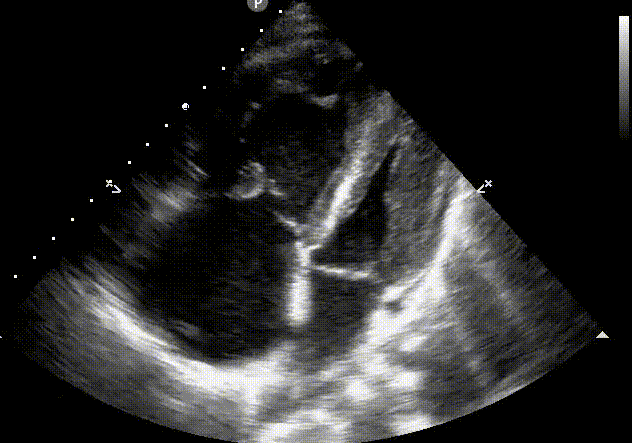

this image demonstrates how to obtain and measure what diastolic parameter:

d. isovolumic relaxation time